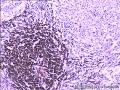

一般病史男性,30岁。因腹痛、腹胀伴乏力、呕吐、腹泻1+月入院。 查体:体温波动在37-39℃,肝脾肋下触及不满意,移浊(-),余未见明显异常。CT 示:腹膜后淋巴结广泛肿大。血常规:WBC;9.1×109/L,RBC;2.2×1012/L,PLT;190×109/L。

大体所见骨髓涂片:有核细胞增生明显活跃,粒红比1.8∶1,减低,粒系统尚可,各阶段细胞偏大,成熟红细胞大小不均,以小细胞为主,淋巴细胞形态正常,意见:感染性骨髓。 大体发现:腹腔淋巴结灰红淡黄结节,1cm×1cm×0.5cm,切面灰白。

免疫组化: CD20 (-)              CD79a (-)

CD3 (-)              CD43 (-)

CD15 (-)              CD30 (+)

CD34 (-)              S-100 (-)

HMB45 (-)              CK (-)

EMA (-)              CD68 (+)

Ki-67   (+,<3%)

肉芽肿性病变。需要结合检验科做病原学检测进一步分析和诊断。